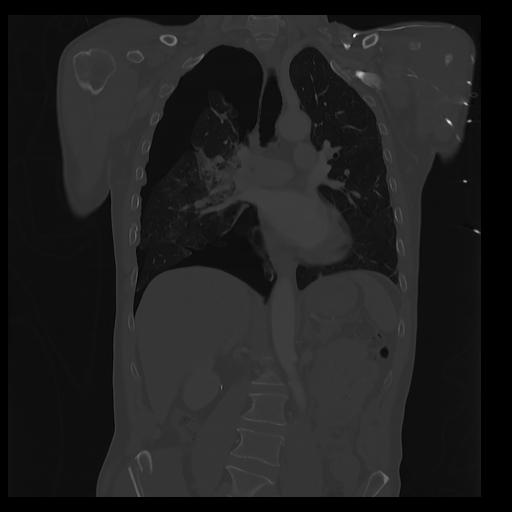

32 PULMON,CE,Coronal,3.000,PULMON,Coronal,